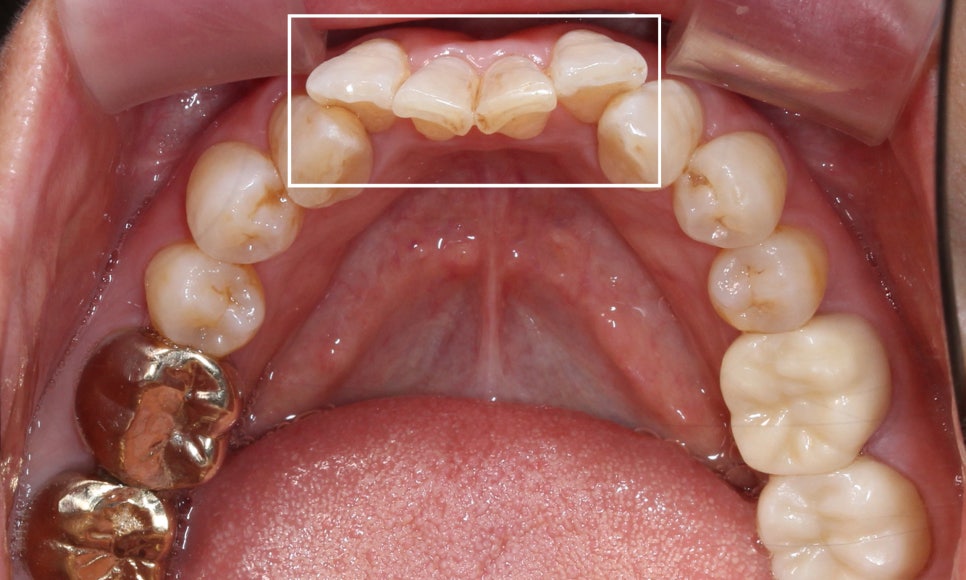

환자분의 아랫니 상태를 보시면

위처럼 앞쪽의 치아들이

심하게 삐뚤거리는 모습인데요,

치아 사이의공간이 좁아서

작은앞니(측절치)의 각도가

심하게 회전된 모습입니다ㅠㅠ

전체적인 아랫니의 치열도

심하게 삐뚤거렸던 처음 모습과 달리

아랫니 부분교정(2D교정)으로

이상적인 치아의 배열인 U-자 곡선의

형태로 바뀐 모습인데요!